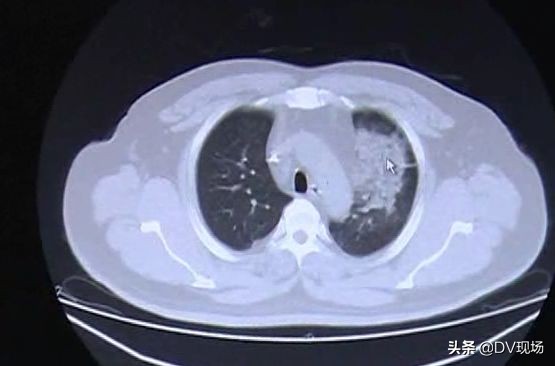

不仅肌酐指数高,他们身体出现的不良状况更加可怕,排尿困难、下肢水肿,张先生更是出现肾脏肿大,双肺渗出严重,出现血氧下降、提示呼吸功能障碍。